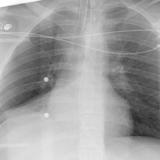

RLL collapse 4 PA

Date: 03/02/2006

Views: 3185